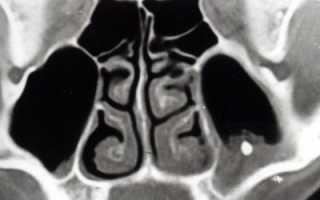

Рентгеновский снимок

После осмотра больному предоставляется возможность сделать рентген гайморовых пазух или МРТ.